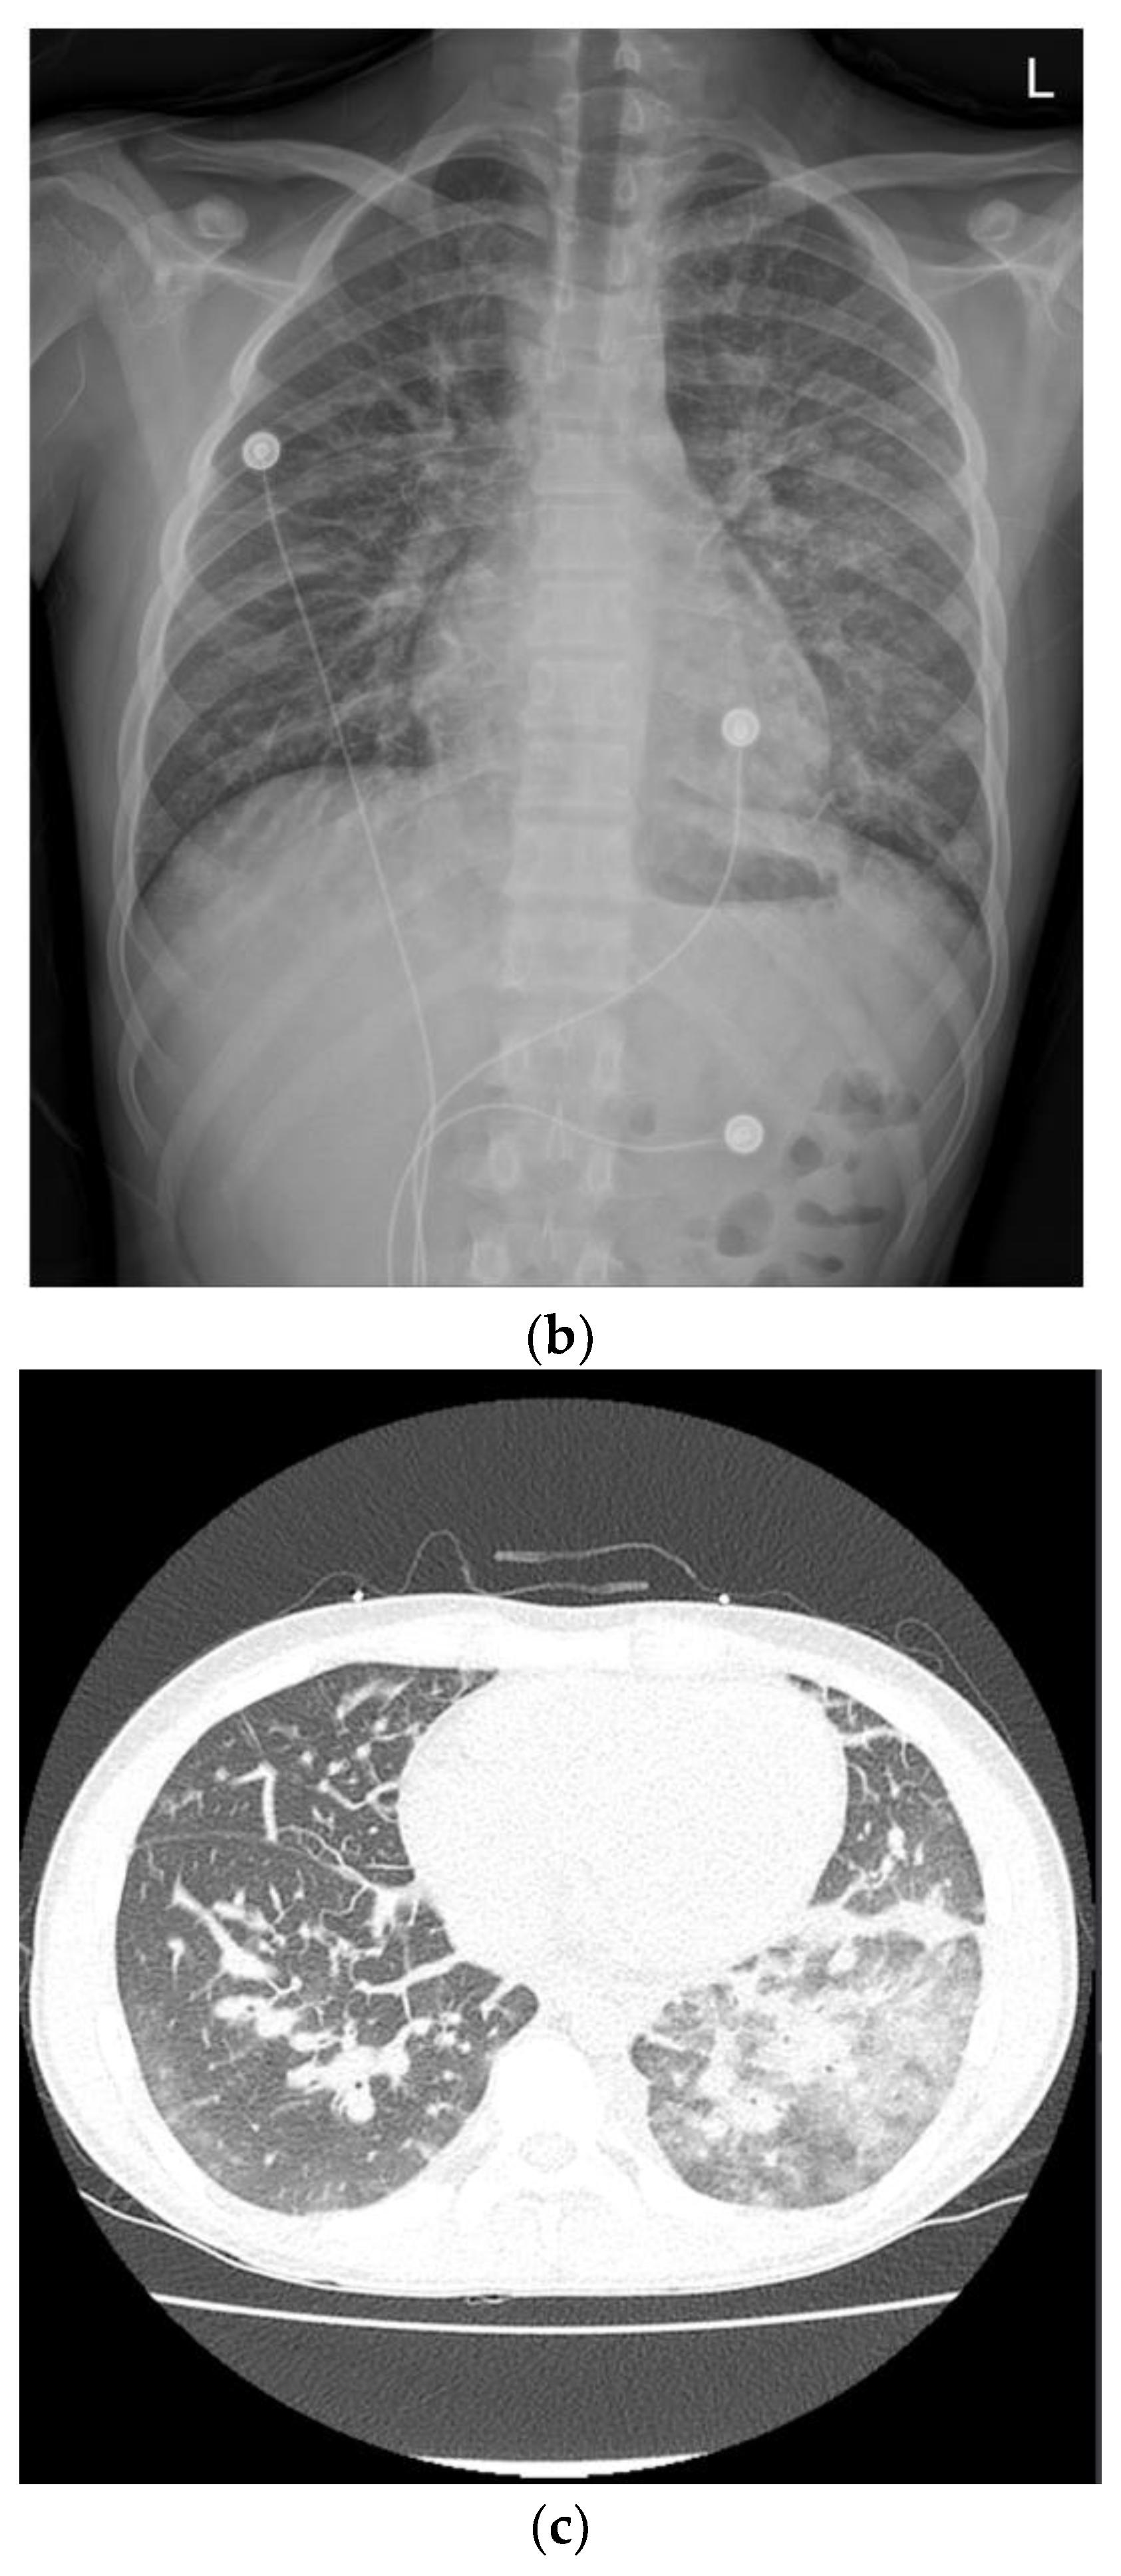

On the third day in the ICU, the patient had massive hematochezia (900 cc), which was the first episode of bloody stools. Vital signs were stable, and no sources of acute bleeding, such as extravasation or pseudoaneurysms, were observed on CT. On colonoscopy, ulcerations were observed in the distal terminal ileum and ileocecal valve. Although observation of the colonic mucosa was limited to blood, there was no focus of active bleeding (Figure 3).

Figure 3.

Initial endoscopic findings revealed ulcerations around the ileocecal valve.